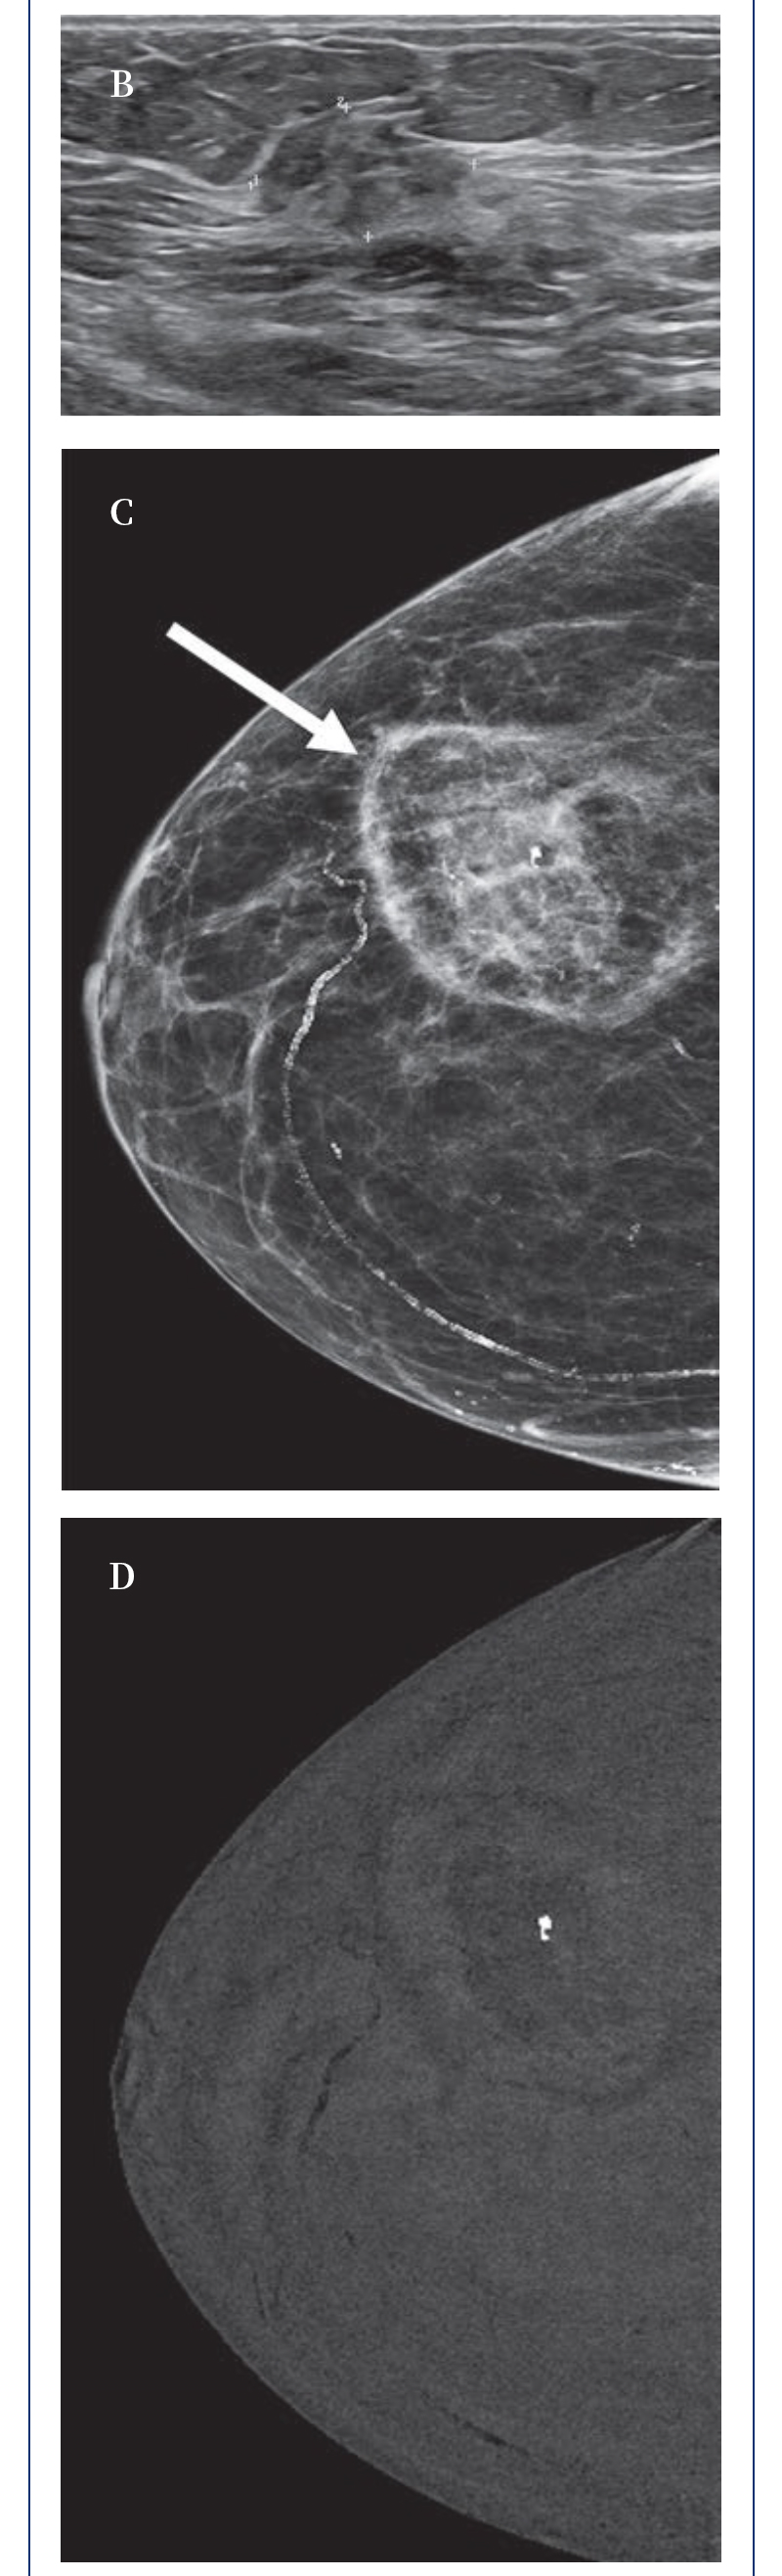

【HYGEA·科研資訊】乳腺癌冷凍消融